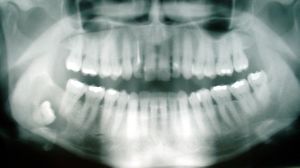

The upper left (picture right) and upper right (picture left) wisdom tooth are distoangularly impacted. The lower left wisdom tooth is horizontally impacted. The lower right wisdom tooth is vertically impacted (unidentifiable in orthopantomogram).